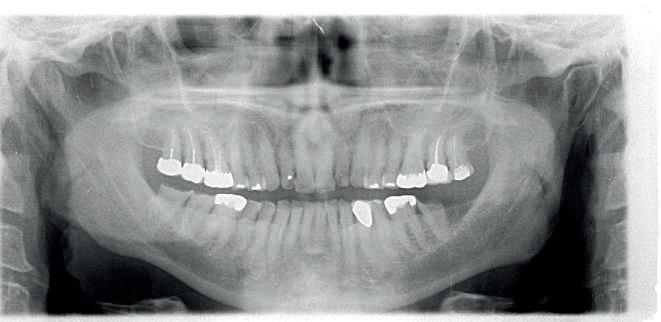

Examinarea parodontală a relevat sângerări generalizate la sondare și adâncimi de sondare de până la 9 mm la molarii maxilari și mandibulari, cu multiple furcații implicate la fiecare molar (fig. 2-7). Prezenta mobilitate multiplă de clasa I la dinții posteriori și de clasa II la dinții nr. 16 și 21 (molarul prim maxilar drept și incisivul central maxilar stâng).

2-4. Imagini înainte de tratament: lateral dreapta (fig. 2), frontal (fig. 3) și lateral stânga (fig. 4). Notă: Molarul prim maxilar drept (dintele 16) (fig. 2) ar fi identificat ca fiind molarul cel mai afectat parodontal care era planificat să fie menținut.

Figurile:

5, 6. Imagini ocluzale înainte de tratament: maxilar (fig. 5) și mandibulă (fig. 6).

7. Rx periapicale înainte de tratament.

8. Rx periapicală a molarului prim maxilar drept (identificat ca fiind molarul cel mai afectat parodontal care era planificat să fie menținut pe arcadă).